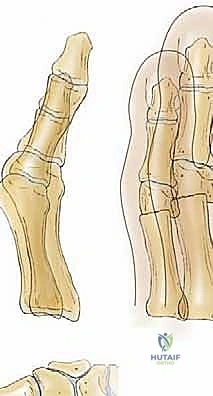

- عظم المشط الأول (First Metatarsal): يُعد هذا العظم حجر الزاوية والدعامة الأساسية في القدم الأمامية. في حالات إبهام القدم الأروح اليافع، غالباً ما نلاحظ حالة تُسمى "تقوس المشط الأول للداخل" (Metatarsus Primus Varus). هذا يعني أن عظم المشط الأول ينحرف بقوة نحو الجانب الداخلي للقدم مبتعداً عن المشط الثاني. هذا الانحراف غالباً ما يكون مصحوباً بـ "ميلان في مفصل العظم الإسفيني الإنسي والمشط الأول" (Obliquity of the Medial Cuneiform–First Metatarsal Joint)، مما يساهم في تكريس وضعية التقوس. "البروز الإنسي" أو "الوكعة" الذي يراه المريض هو في الواقع الجزء البارز من رأس عظم المشط الأول المنحرف.

- السلامية الدانية (Proximal Phalanx): هي العظمة الأولى في إصبع القدم الكبير، وتتصل برأس المشط الأول لتشكل "مفصل المشط السلامي الأول" (MTP joint). هذا المفصل هو ساحة المعركة الحقيقية حيث يحدث "انحراف إبهام القدم الأروح" (Hallux Valgus Angulation).

- العظام السمسمية (Sesamoid Bones): هما عظمتان صغيرتان جداً تقعان أسفل رأس المشط الأول. تعملان كبكرة لتسهيل حركة الأوتار وتوزيع الضغط أثناء المشي. في حالة الإبهام الأروح، تنزلق هذه العظام من مكانها الطبيعي مما يزيد من تعقيد التشوه.

- صفائح النمو (Physes): كما ذكرنا، هي السمة المميزة لليافعين. في عظم المشط الأول، تقع صفيحة النمو الرئيسية في القاعدة (الجزء القريب من الكاحل). لذلك، يجب أن تتم أي جراحة بحذر شديد لتجنب هذه المنطقة.